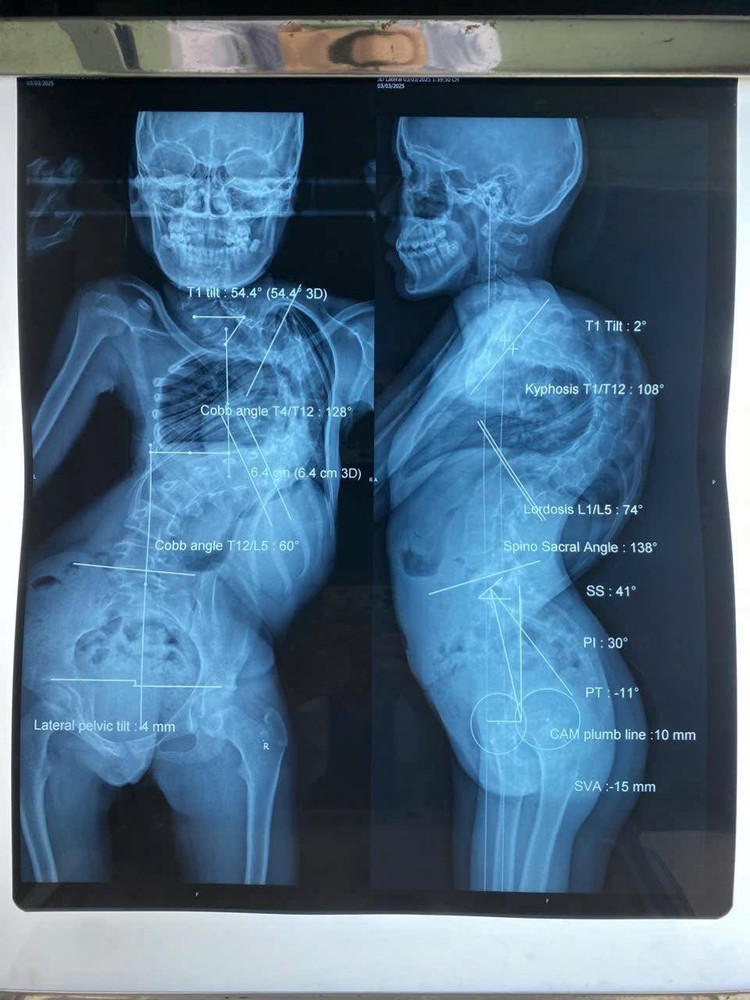

Khác với bé L., thách thức của bé Y.T (13 tuổi) đến từ thể trạng quá yếu. Bé chỉ nặng 28 kg do suy dinh dưỡng nặng, mắc hội chứng hạn chế hô hấp, cột sống cong đến 128 độ và gù 108 độ khiến lồng ngực bị chèn ép liên tục, chỉ có thể nằm sấp khi ngủ.

Hình ảnh cột sống cong vẹo trên phim chụp của các bệnh nhi - Ảnh BVCC